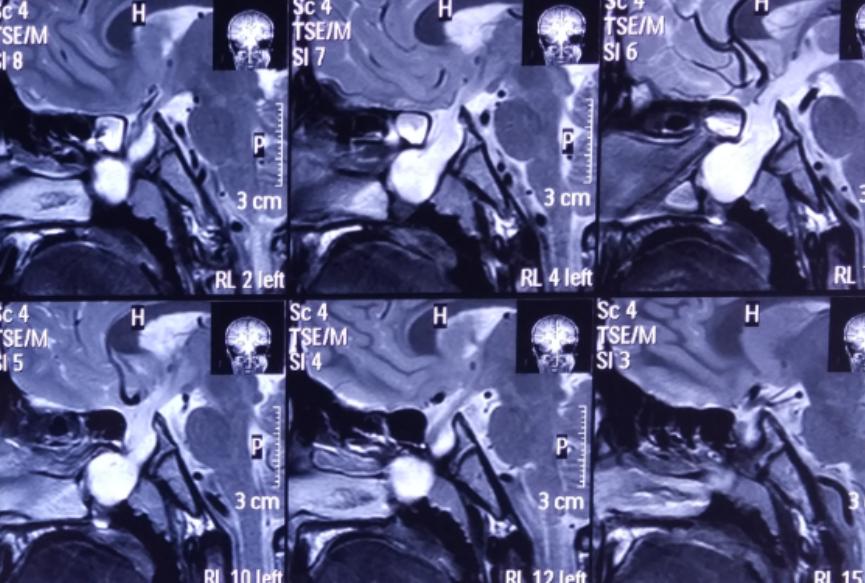

影像资料